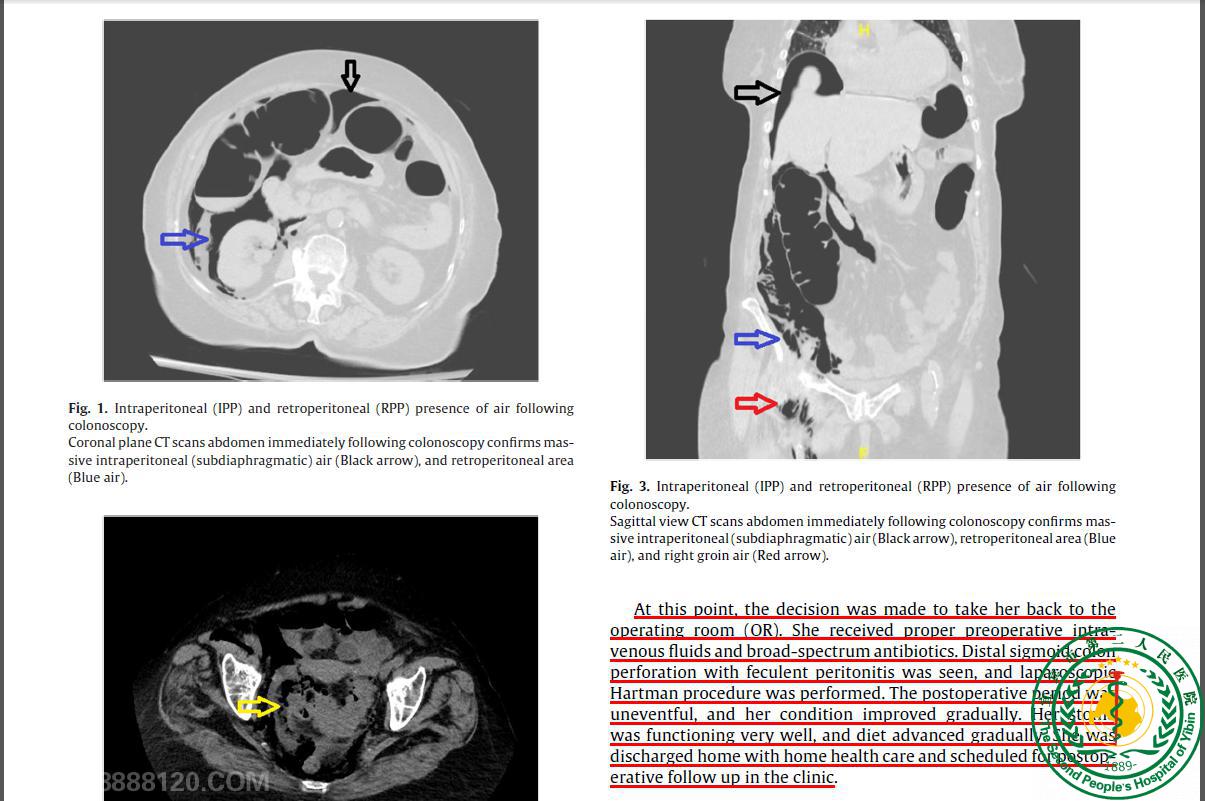

Pneumoretroperitoneum with subcutaneous emphysema after a postcolonoscopy colonic perforation

Pneumoretroperitoneum with subcutaneous emphysema after a postcolonoscopy colonic perforation21661